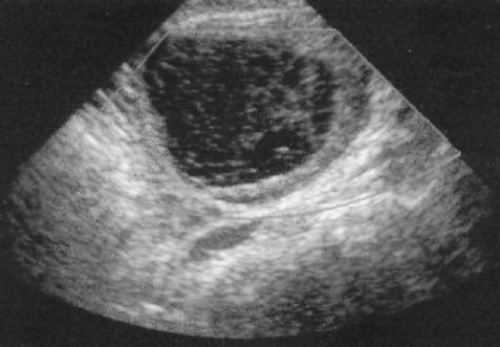

Часто визуализируется тонкостенная киста, размером 2,5-8,5 см, с множественными внутренними перегородками – «паутина» или «полотно рыболовной сети» (фото 2). Цветовая допплерография не выявляет кровоток перегородок (визуализируются как фиброзные тяжи).

Фото 2. Геморрагическая киста яичника – классический вид «рыболовной сети». В отличие от эндометриоидных кист, геморрагические кисты характеризуются минимальным акустический эффектом усиления

Кистозные массы с сокращающимся периферическим сгустком, кисты с жидкостью или кисты с неоднородной или толстой стенками обнаруживаются реже.